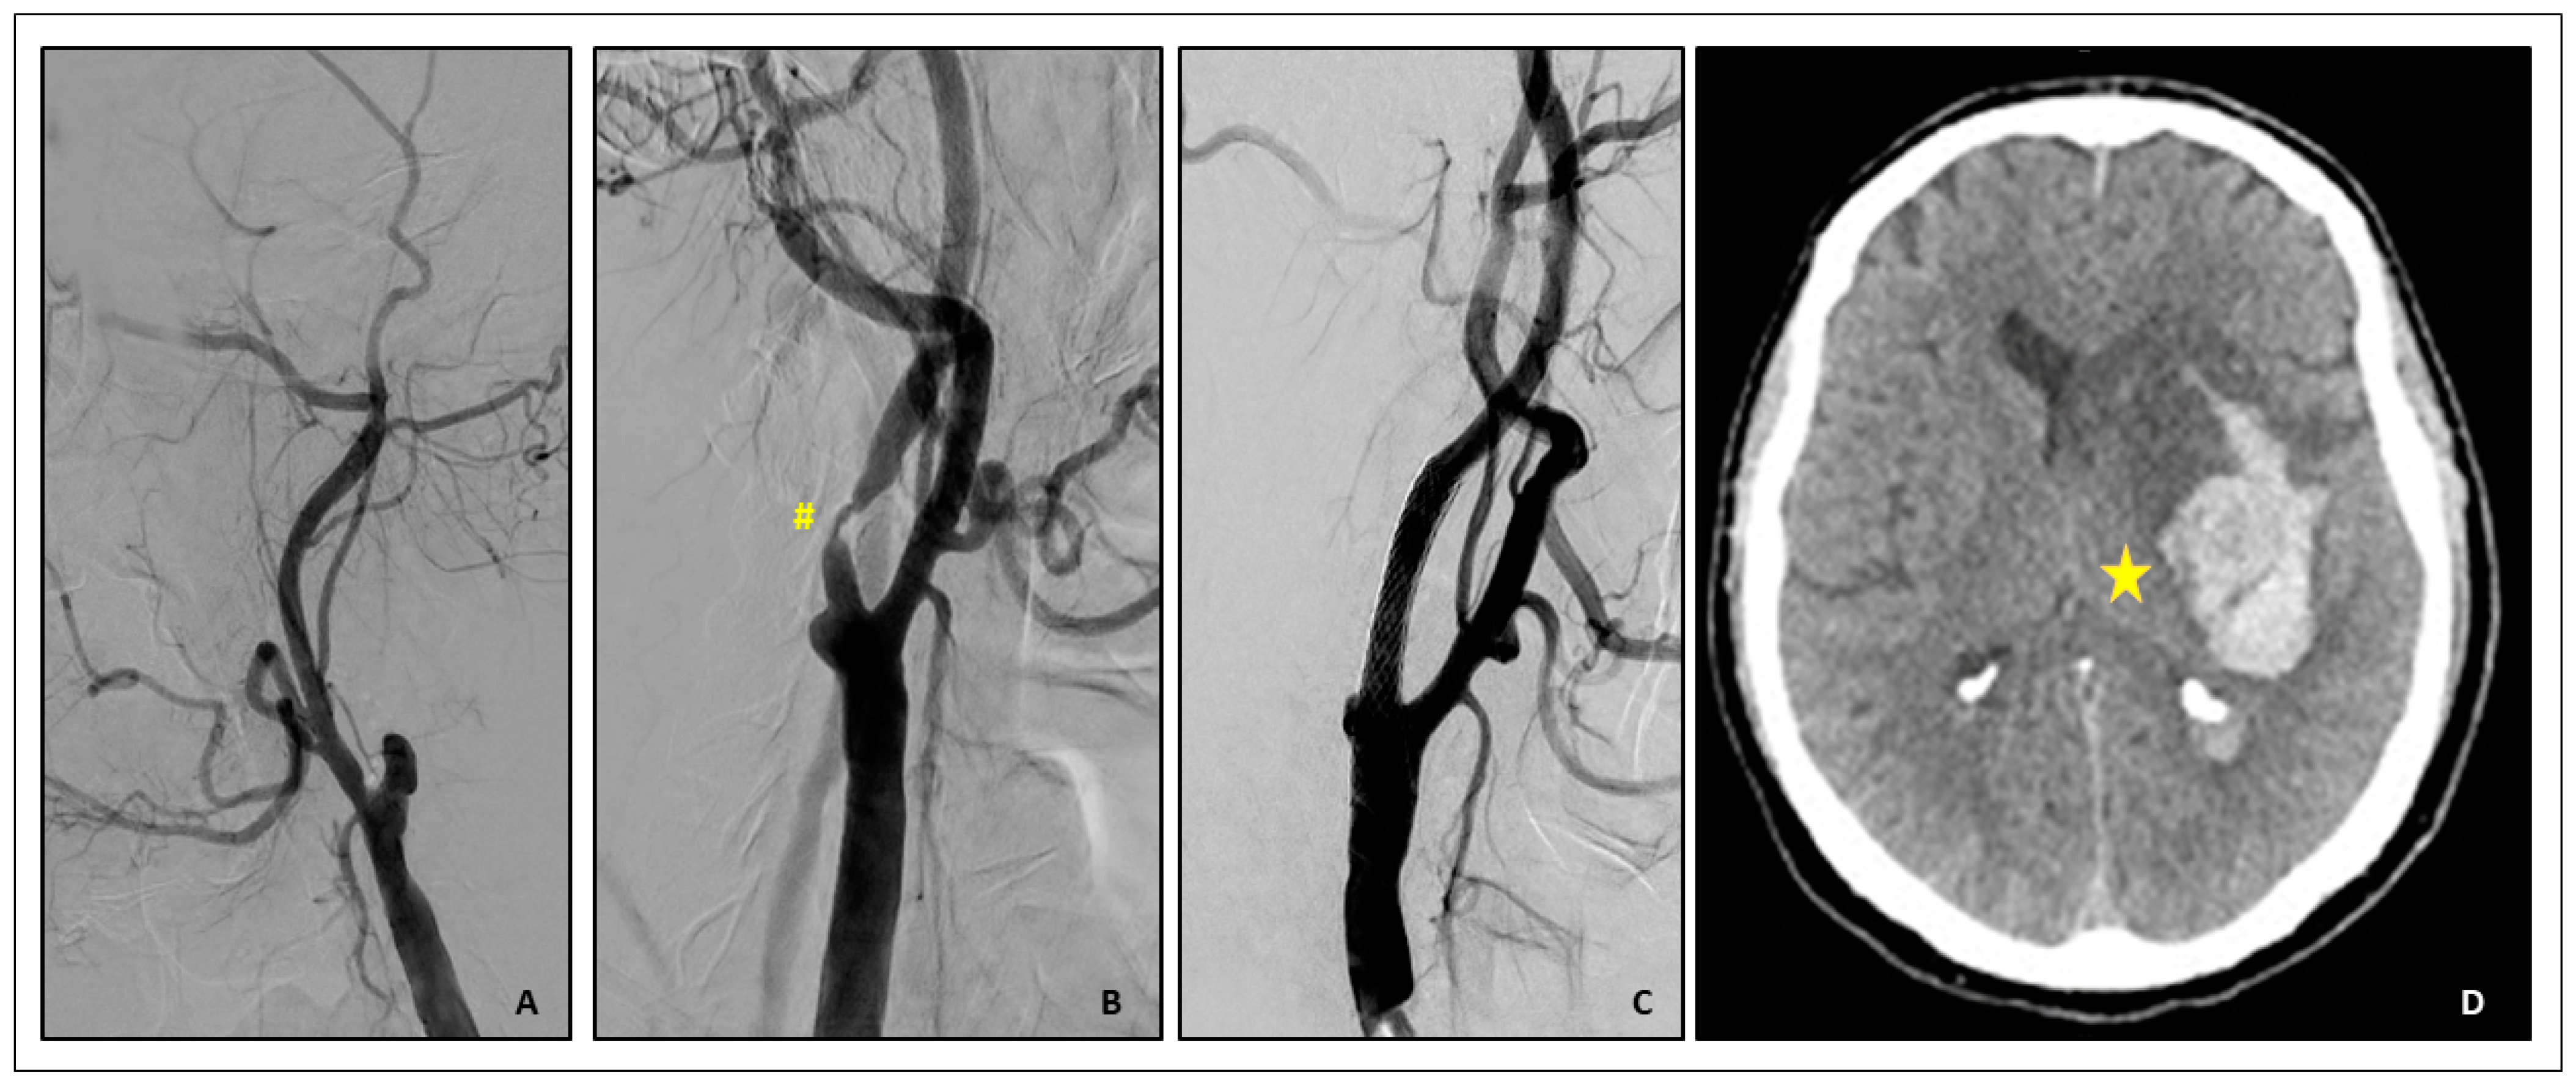

- (1)

- Acute Carotid Stent thrombosis:

- Brief Case description:

- Cerebral hyperperfusion syndrome (CHS)

- Brief case description